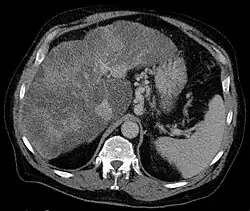

Gastric varices are dilated submucosal veins in the lining of the stomach, which can be a life-threatening cause of bleeding in the upper gastrointestinal tract. They are most commonly found in patients with portal hypertension, or elevated pressure in the portal vein system, which may be a complication of cirrhosis. Gastric varices may also be found in patients with thrombosis of the splenic vein, into which the short gastric veins that drain the fundus of the stomach flow. The latter may be a complication of acute pancreatitis, pancreatic cancer, or other abdominal tumours, as well as hepatitis C. Gastric varices and associated bleeding are a potential complication of schistosomiasis resulting from portal hypertension.